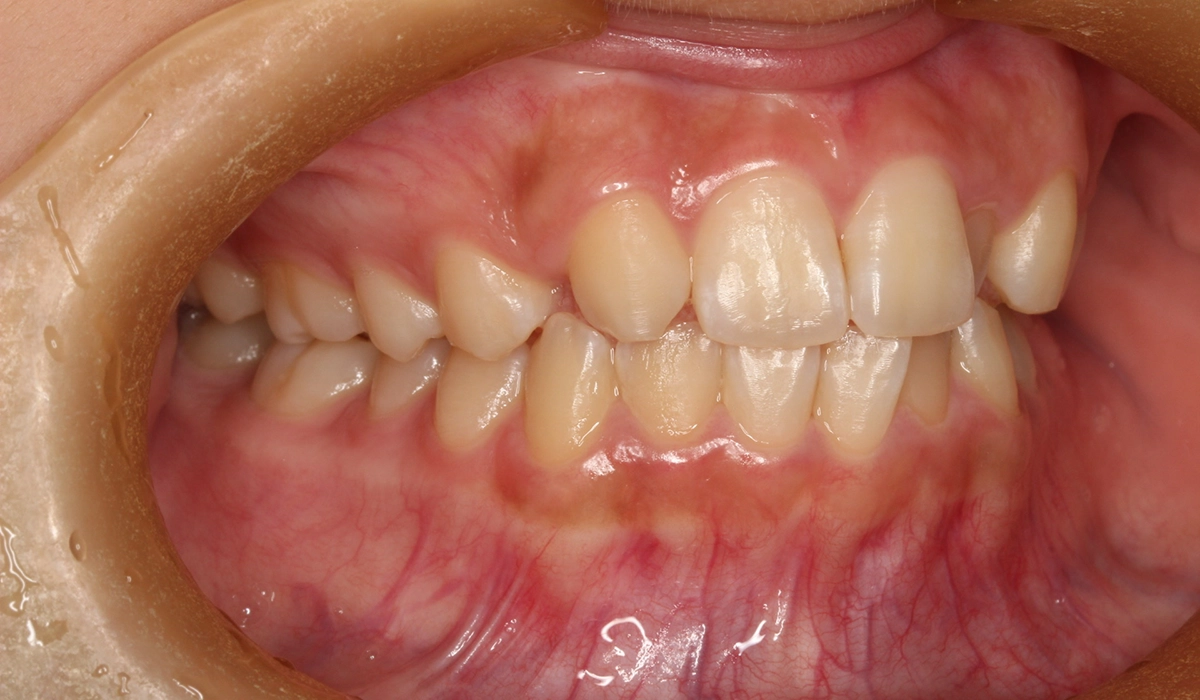

術前:右側

今回ご紹介する患者様は、上顎の歯並びのがたつきを気にされており、矯正検査後Ⅰ級叢生と診断いたしました。矮小歯があるため個性を生かして配列。

| 治療内容 | 上顎の歯並びのがたつきを気にされており、矯正検査後Ⅰ級叢生と診断。矮小歯があるため個性を生かして配列。 |